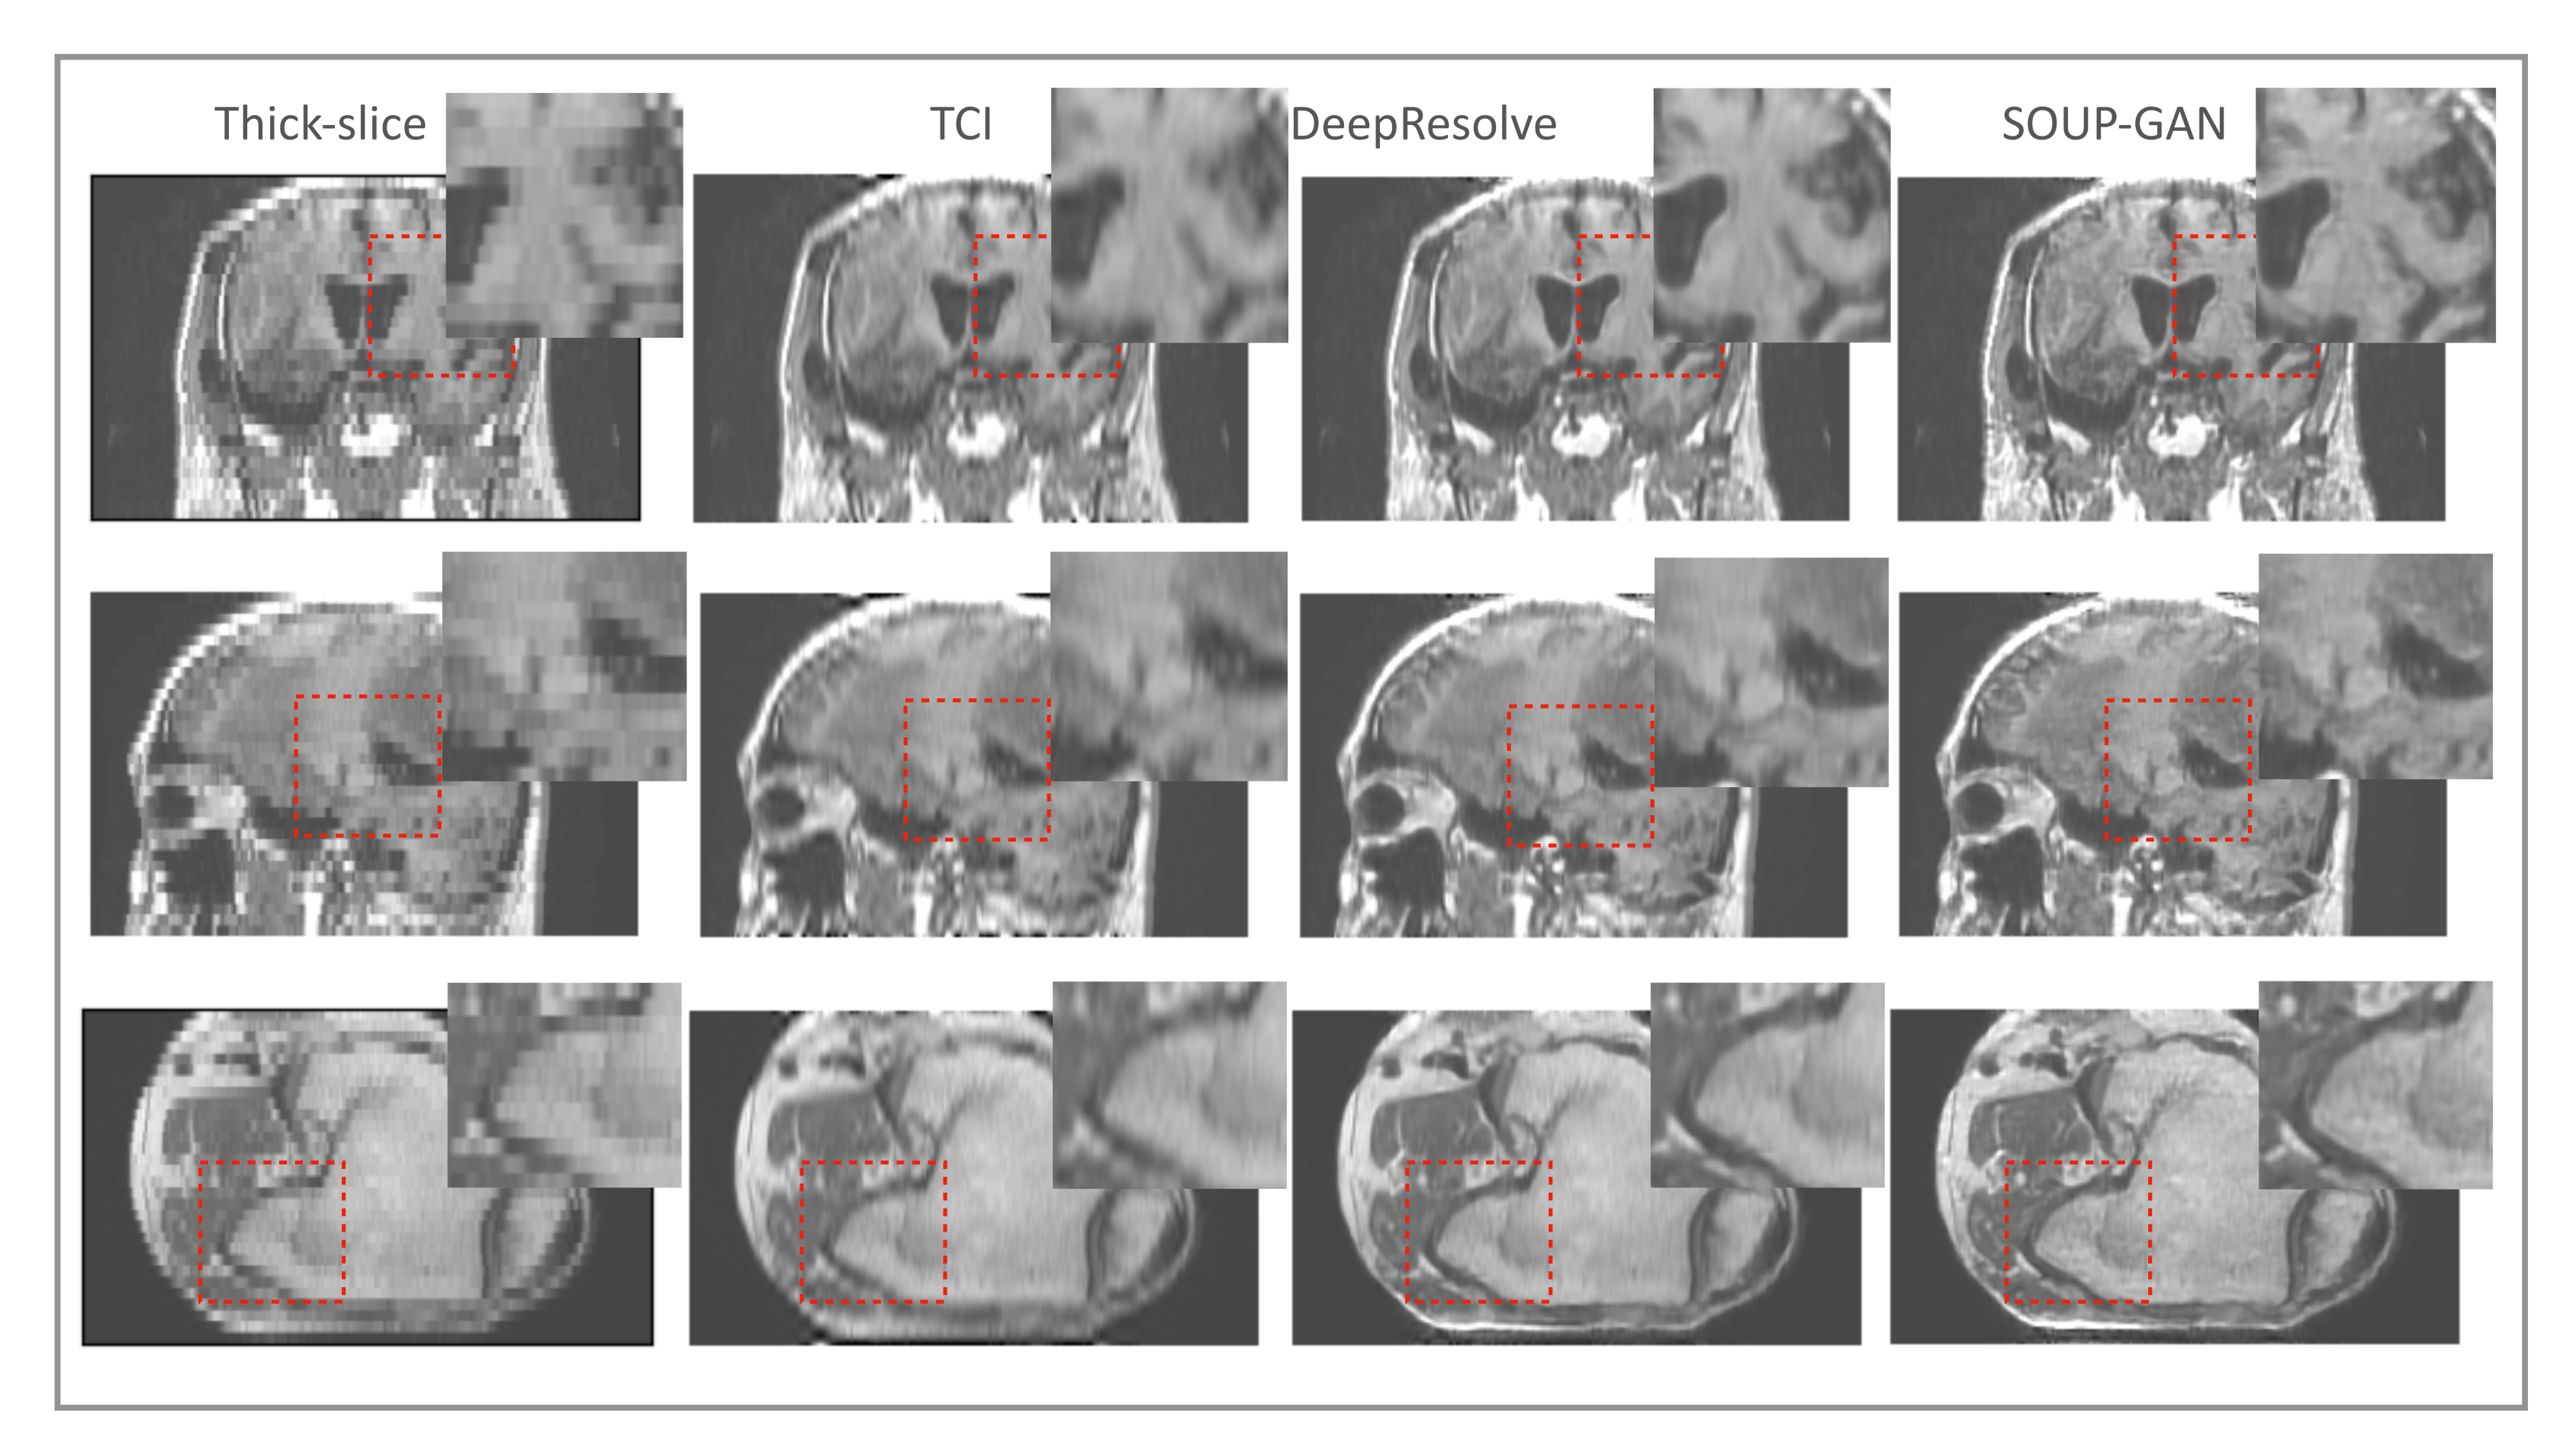

As discussed in Section 2, pixel-wise loss usually achieves a relatively high metric score but fails in resolving the textures, edges, and high-frequency details, resulting in blurring of the images that are produced. The scheme that we propose generalizes the application of perceptual loss previously defined on 2D pre-trained VGG to study single-image SR onto 3D medical images. Through this simple but effective idea of importing all the projected slices along the three principal directions into the pre-trained VGG, we observed that the 3D MRI volume can be perceptually resolved (see the ablation study Figure 8). SOUP-GAN was compared to another MRI SR approach called “DeepResolve”, both of which focus on thick-slice to thin-slice reconstruction. The two test datasets included in Figure 8 are the T1-weighted brain MRI (reformatted coronal images in the first row, and reformatted sagittal images in the second), and knee MRI in the third row. The images appear better compared to the original thick slices, the cubic-spline interpolated images, and the MSE results. They are further improved by 3D perceptual loss with GAN, achieving the highest perceptual quality. Besides the three principal directions (e.g., axial, sagittal, and coronal), we noted that oblique planes are also able to be resolved through multi-planar reconstruction with our 3D perceptual-loss strategy (unpublished data). We used a ’vanilla’ GAN instead of more advanced GANs, e.g., Wasserstein [45] or Relativistic GAN [46], since the vanilla GAN performs well for our training.

Figure 8.

Ablation study: Test examples on brain and knee MRI showing perpendicular reconstructions from original thick slices, using TCI, MSE, and GAN using 3D perceptual loss (SOUP). We note that [32] proposed a single-scale residual-based 3D convolutional neural network with MSE, similar to the third column here. Our SOUP approach better resolves the perceptual details and is more generally applicable to various sampling factors and different imaging modalities. TCI: tricubic interpolation.